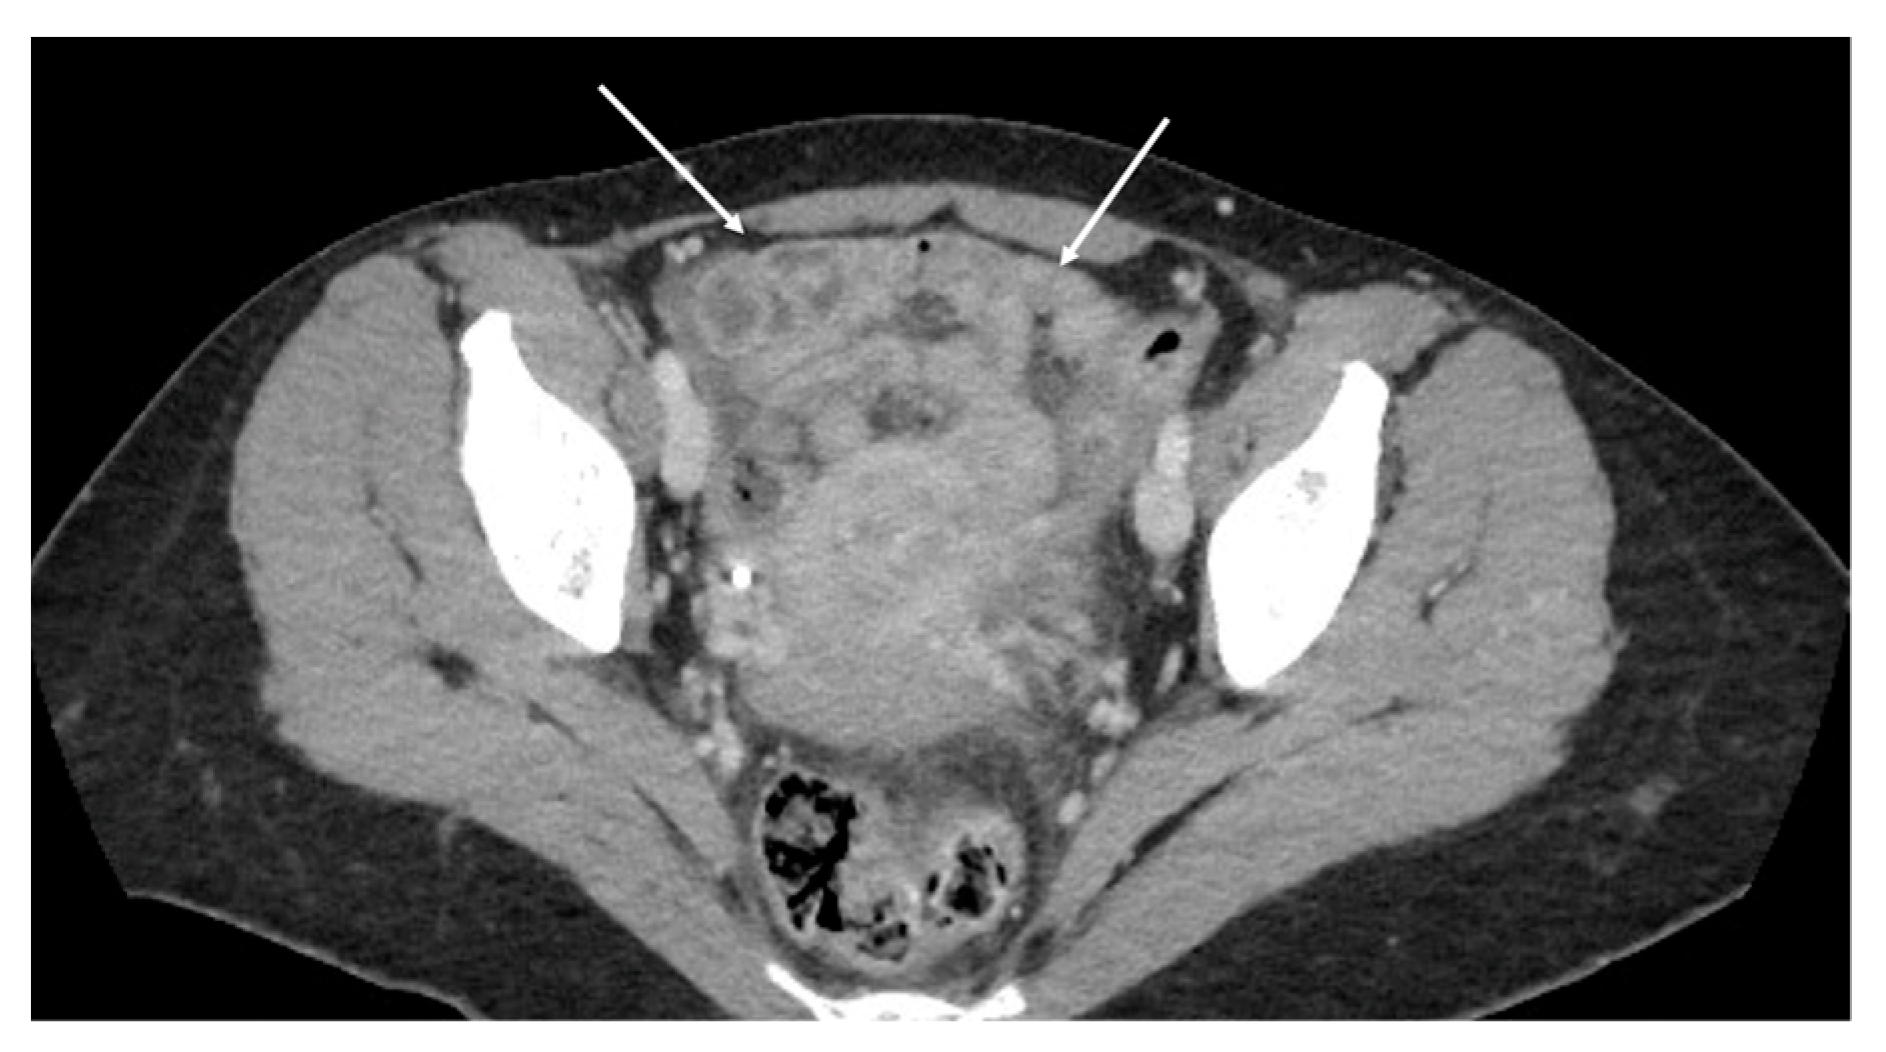

- Theca pattern: characterized by a nodular thickening of the visceral peritoneum lining the loops of the small bowel. Sometimes, this heteroplasic thickening generates narrowing, with the consequent obstruction and dilation of the proximal loops, a condition also referred to as “frozen pelvis” [95] (Figure 12).